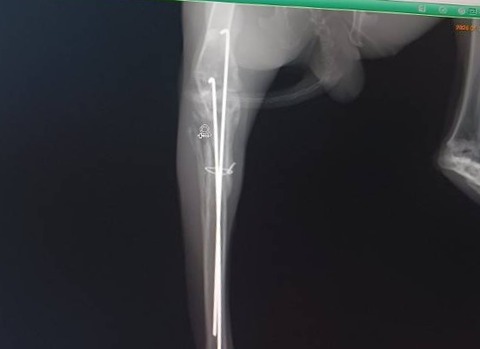

2025年11月に右後ろ脚を骨折し、11/14にピンニング手術を受け、現在も経過観察中です。

1/10 経過の診察を受けました。

足の曲げ伸ばしや太ももの筋肉の状態は良好で、まだ力は弱いものの、自分の足で押し返そうとする反応が見られました。

レントゲンでは骨の形成は概ね順調でしたが、固定していたピンのうち1本が抜けてきていることが確認されました。

このため、早めにピンを抜去する方針となりました。

1/14 ピン抜去手術

予定通り2本のピンを抜去し、手術は大きな問題なく終了しました。

足の可動は保たれているものの、レントゲン上では膝の骨がやや前方に出ており、過去に靭帯を損傷していた可能性があるとの説明を受けました。

将来的に関節への負担が出る可能性はありますが、現時点では慎重に経過を見ていくことになりました。

術後は運動量を制限し、内服薬を使用しながら回復を待ちます。

帰宅後はカラーで不自由そうにしながらも、牧草を食べ、排泄も確認。

早めに処置ができたことで、断脚に至らずに済んだことは大きな救いでした。

1/20 抜糸と経過を診ていただき、傷の状態は良好でした。

右後肢の筋肉はもう少しついてほしいものの、足裏の汚れから、少しずつしっかり使えてきている様子がうかがえます。

今後は様子を見ながら、生活スペースを徐々に広げていく予定です。

次回は2/10にレントゲン検査を行う予定です。

カラーが外れ、はるくんが少しでも快適に過ごせる時間が増えていくことを願いながら、引き続き見守っていきます。